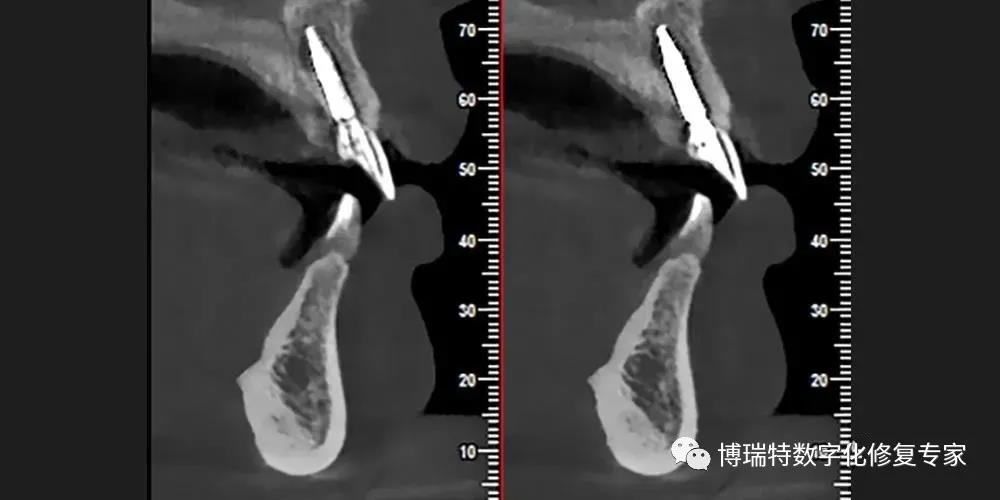

8226; CBCT检查显示11,12见根颈1/3根折线,无明显移位;

8226; 21根颈1/3根折,冠向移位,唇侧骨板完整,厚度约1mm,根尖区骨量充足;

8226; 22根长约9mm。